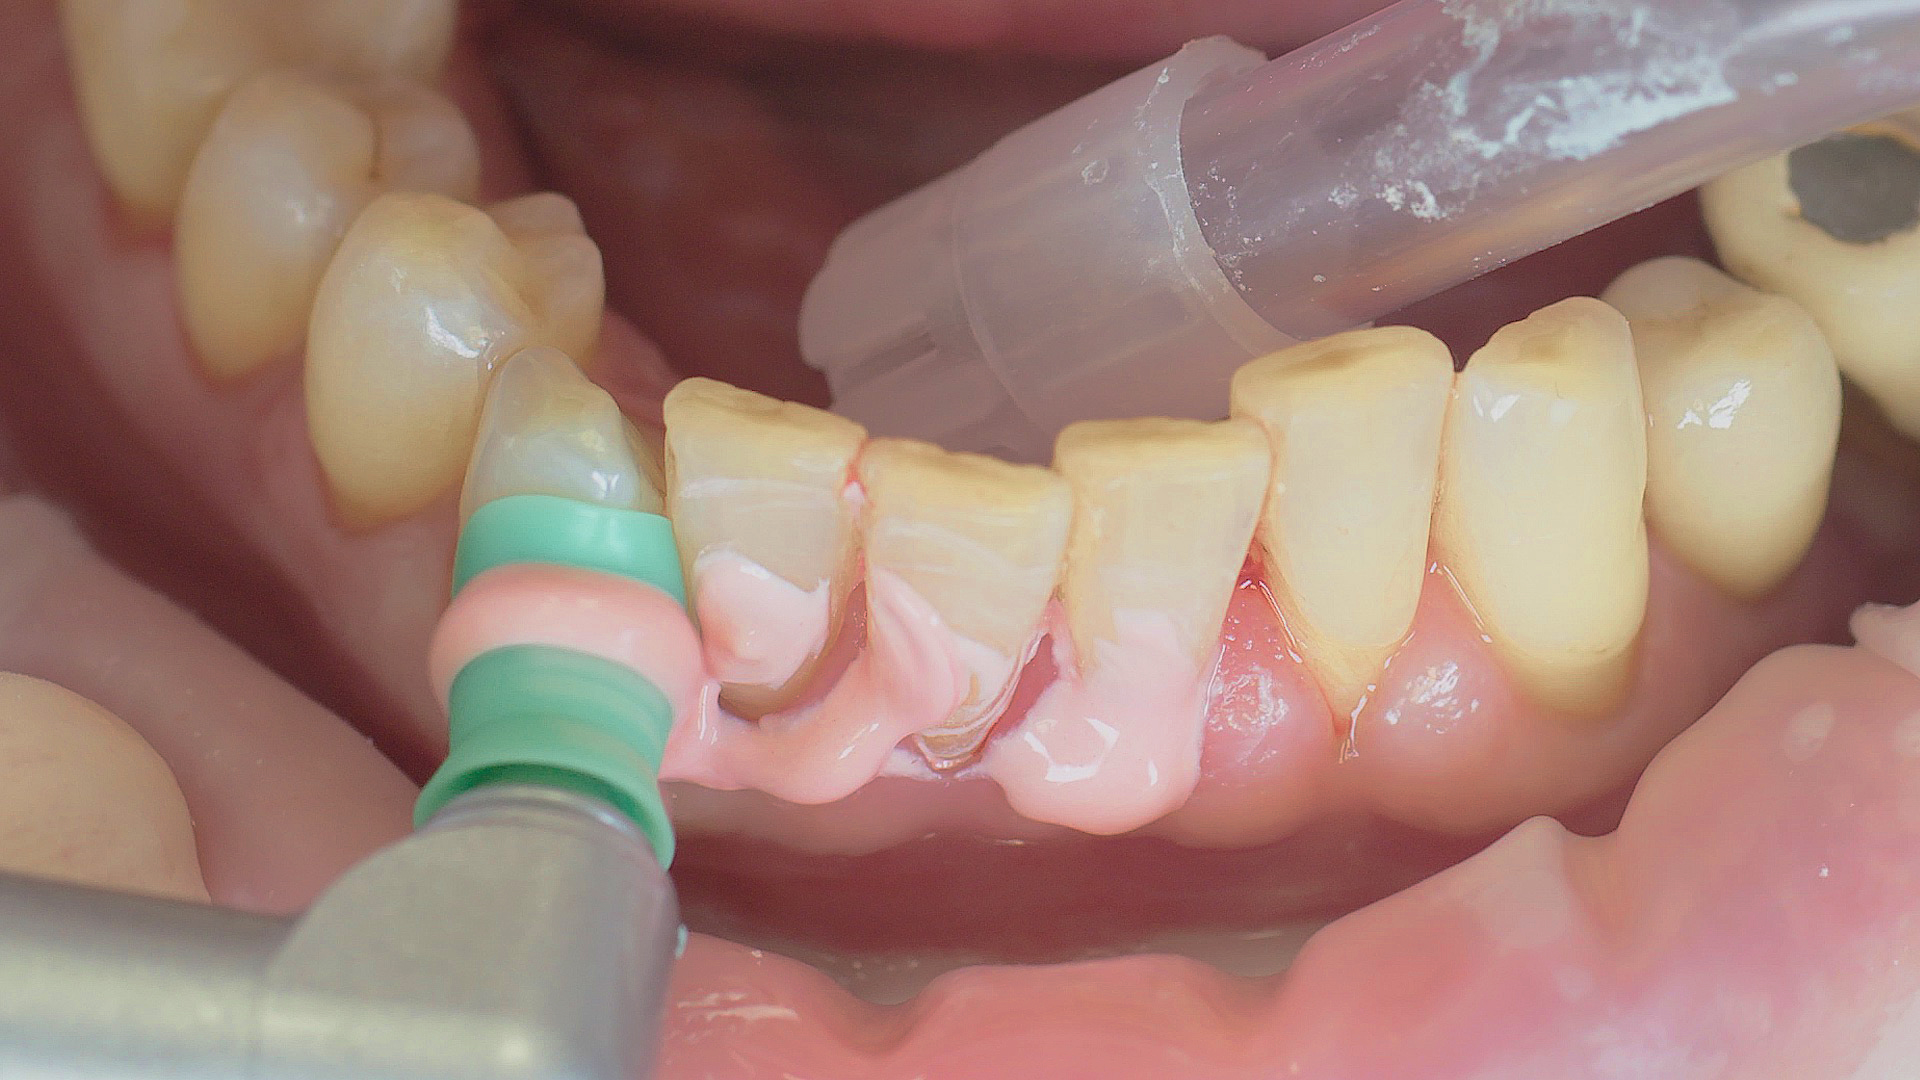

Removal of subgingival coatings (debridement) is carried out using sonic or ultrasonic devices and special periodontal tips as initial periodontal treatment (Fig. 3). Manual instruments can also be used. Further surgical and/or regenerative measures may be necessary, depending on the situation.

Sonar technology, W&H Proxeo with 1AP tip

Fig. 3: If marginal periodontitis is diagnosed, the initial debridement can be carried out very efficiently with an air scaler (sonar technology, W&H Proxeo with 1AP tip)